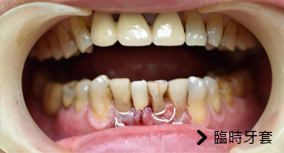

植牙+假牙同天執行

客戶因牙齒自然汰換,有植牙及假牙需求,舊牙因功能毀壞無法使用,故與亞德醫師約定時間,於同日植牙後,醫師再協助其製作一個臨時假牙,以利其後續正常進食及治療,有效維持生活品質。